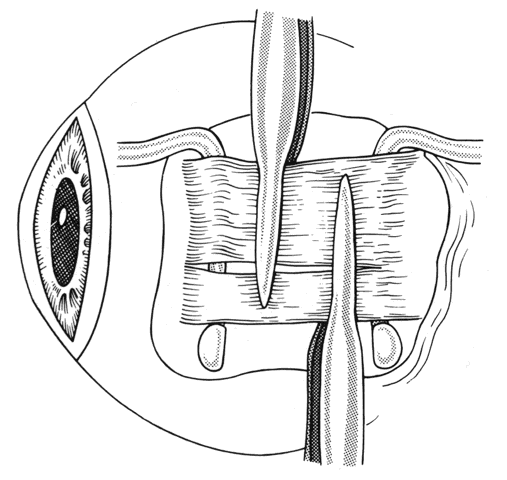

If a rectus muscle has been recessed 5 mm or more, further recession will put the new insertion at or beyond the arc of contact of the rectus muscle and the globe. This may cause decreased function of the muscle and produce noncomitant ocular rotations, especially in extreme gaze positions. To weaken a rectus muscle without disturbing its insertion site, a marginal myotomy can be performed.39,40 Usually, two separate cuts are made into the muscle near the tendon (Fig. 36) until the muscle lengthens. The weakening effect can be graded by increasing the number of cuts from two to three or by increasing the percent of the muscle that is cut. To be effective, a marginal myotomy should be accompanied by resection of the ipsilateral antagonist muscle.

Fig. 36. To perform a marginal myotomy, the muscle tendon is gently stretched between two Jameson muscle hooks. Prophylactic hemostasis is achieved by clamping the muscle or by application of a wet-field cautery to blanch the vessels in the tendon. The muscle is cut with small “snips” using a Wescott scissors.